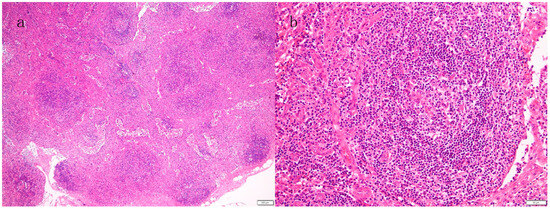

3.2. Histopathological Diagnosis of Lymph Nodes

- Kurose, N.; Futatsuya, C.; Mizutani, K.I.; Kumagai, M.; Shioya, A.; Guo, X.; Aikawa, A.; Nakada, S.; Fujimoto, S.; Kawabata, H.; et al. The clinicopathological comparison among nodal cases of idiopathic multicentric Castleman disease with and without TAFRO syndrome. Hum. Pathol. 2018, 77, 130–138. [Google Scholar] [CrossRef] [PubMed]